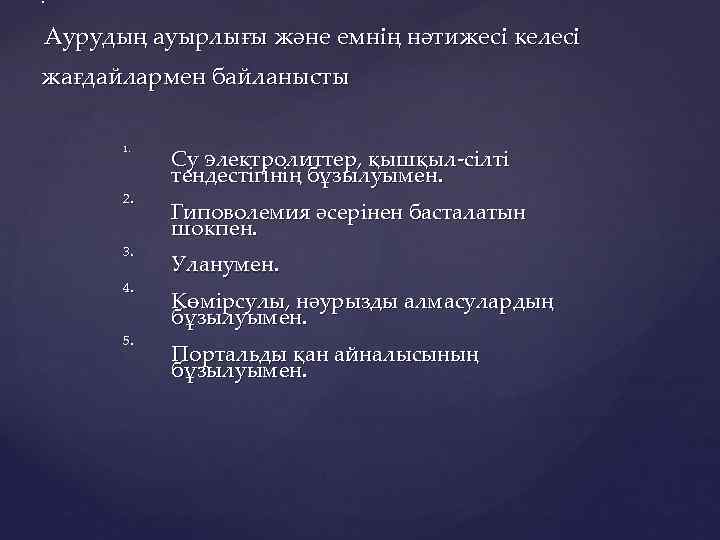

: Аурудың ауырлығы және емнің нәтижесі келесі жағдайлармен байланысты 1. 2. 3. 4. 5. Су электролиттер, қышқыл-сілті тендестігінің бұзылуымен. Гиповолемия әсерінен басталатын шокпен. Уланумен. Көмірсулы, нәурызды алмасулардың бұзылуымен. Портальды қан айналысының бұзылуымен.

Аурудың 3 клиникалық кезеңі бар: Илеустың айқай кезеңі (алғашқы 12 -16 сағат) Улану кезеңі (12 -36 сағат) Терминальды кезең